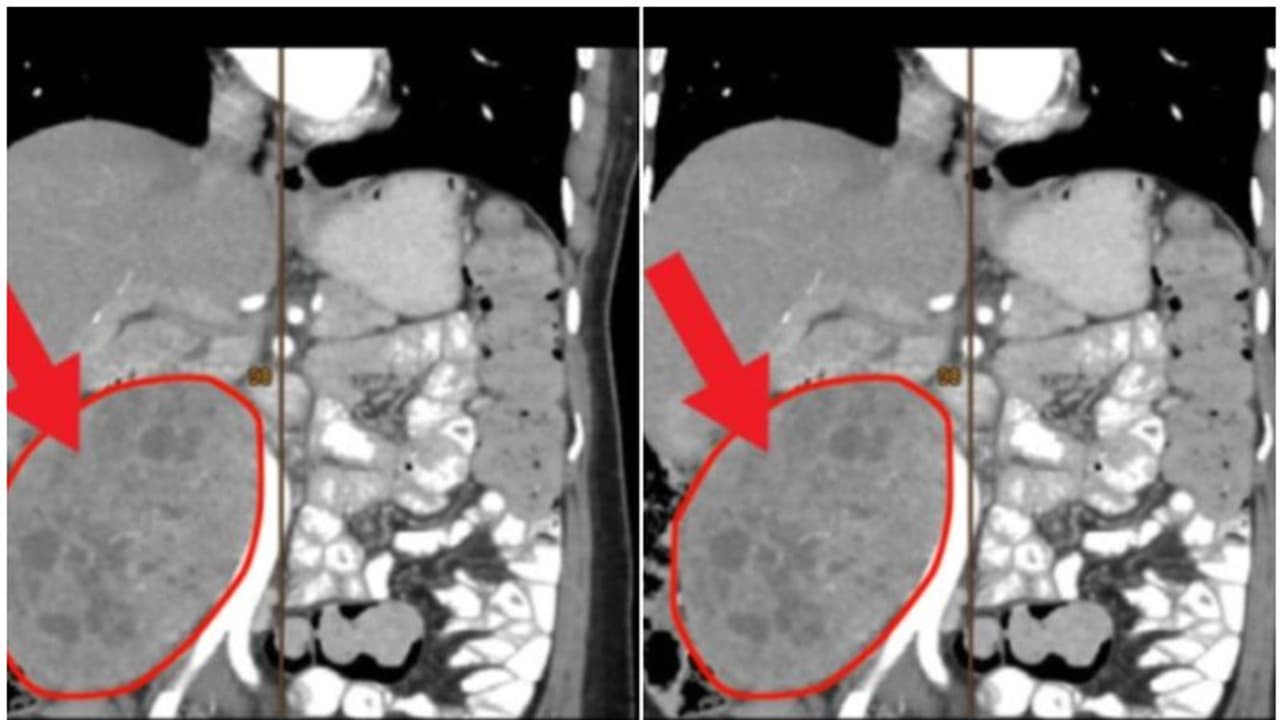

മനാമ: ബഹ്റൈനില് 55കാരിയുടെ വയറ്റില് നിന്ന് രണ്ട് കിലോ ഭാരമുള്ള മുഴ നീക്കം ചെയ്തു. കിങ് ഹമദ് യൂണിവേഴ്സിറ്റി ആശുപത്രിയില് വെച്ചാണ് സ്ത്രീയുടെ ശസ്ത്രക്രിയ നടത്തിയത്. കണ്സള്ട്ടന്റ് ജനറലും ബാരിയാട്രിക് സര്ജനുമായ ഡോ. അബ്ദല് മൊനെയിം അബു അല് സെല്ലിന്റെ നേതൃത്വത്തിലാണ് രണ്ട് മണിക്കൂര് നീണ്ട സങ്കീര്ണമായ ശസ്ത്രക്രിയ പൂര്ത്തിയാക്കിയത്.

വയറുവേദനയുമായാണ് സ്ത്രീ ആദ്യം എത്തിയത്. രണ്ട് മാസത്തിനിടെ പെട്ടെന്ന് ഭാരം കുറഞ്ഞതായും സ്ത്രീ പറഞ്ഞു. ക്ലിനിക്കല് പരിശോധനയിലും കളര് ടോമോഗ്രഫിയിലും സ്ത്രീയുടെ വയറ്റില് മുഴ ഉള്ളതായി കണ്ടെത്തി. കാലം കഴിയുന്തോറും മുഴ അപകടരമാകുന്നതാണെന്ന് ബയോപ്സി റിപ്പോര്ട്ടില് വ്യക്തമാകുകയും ചെയ്തു. തുടര്ന്നാണ് ശസ്ത്രക്രിയ നടത്തി ഇത് പുറത്തെടുത്തത്. കണ്സള്ട്ടന്റ് ജനറല് സര്ജന് ഡോ. ഇജാസ് വാനി, കണ്സള്ട്ടന്റ് വാസ്കുലാര് സര്ജന് ഡോ. റാനി അല് മൊയാറ്റസ് ബില്ലാ അല് അഘ എന്നിവരും ശസ്ത്രക്രിയ നടത്തിയ സംഘത്തിലുണ്ടായിരുന്നു. ശസ്ത്രക്രിയയ്ക്ക് ശേഷം സുഖം പ്രാപിച്ച 55കാരി നാലു ദിവസങ്ങള്ക്ക് ശേഷം ആശുപത്രി വിട്ടു.